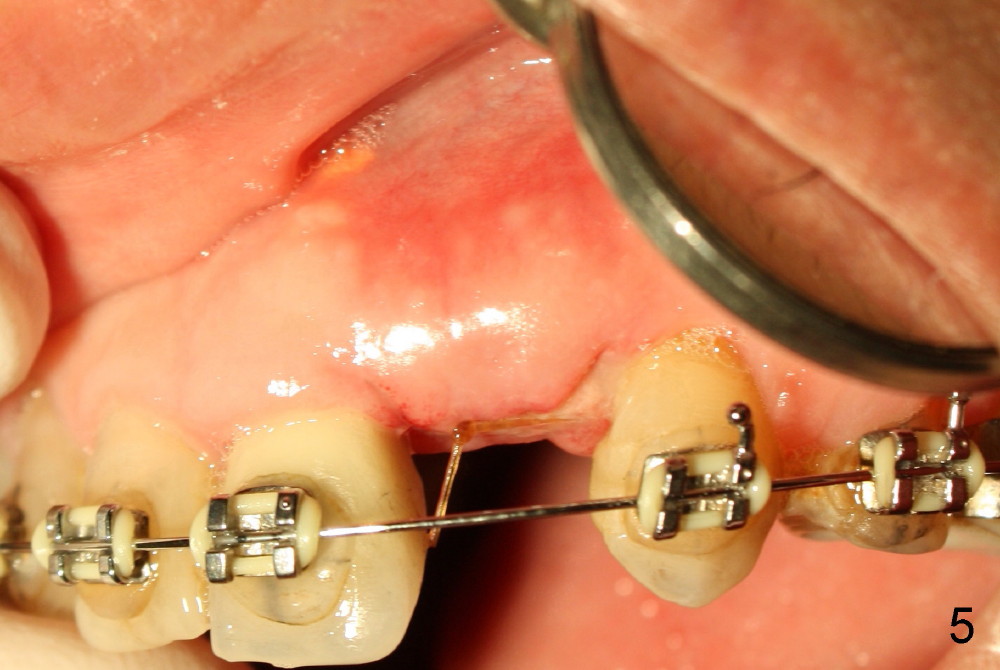

A prominent feature of implant failure in this case is pain. The patient feels that the pain is from the base of the nose. PA taken 3 days postop shows that the implant is inferior to the nasal floor (Fig.2 red ^). Clinically, the buccal gingiva continues to be erythematous 10 days postop (Fig.1). The pain is so unbearable that the implant (3.8x14 mm) is removed 10 days post placement. After repeated debridement, a 4.1 mm tap (Fig.3 T) is manually inserted with torque. A 4.1x14 mm submerged implant is placed with insertion torque < 30 Ncm, but it is placed subcrestally (Fig.4 <--). This time an immediate provisional is not provided. The flap is sutured. The pain disappears immediately. No infection is found 7 days postop (Fig.5). However, an asymptomatic vesicle is noted at the crest 3 weeks postop (Fig.6). The gingiva looks normal 2 and 3 months postop (Fig.7,8). The coronal gap dissolves 3 months postop (Fig.9 >, as compared to Fig.4), suggesting osteointegration. The implant is uncovered 4 months postop (Fig.10). Bracket is placed 5 months postop (Fig.10'). One month later, the left central incisor improves in position coronocervically (Fig.11), but the overjet needs correction by distalization of the upper anterior teeth. The implant at the site of #10 may be used as an anchorage.